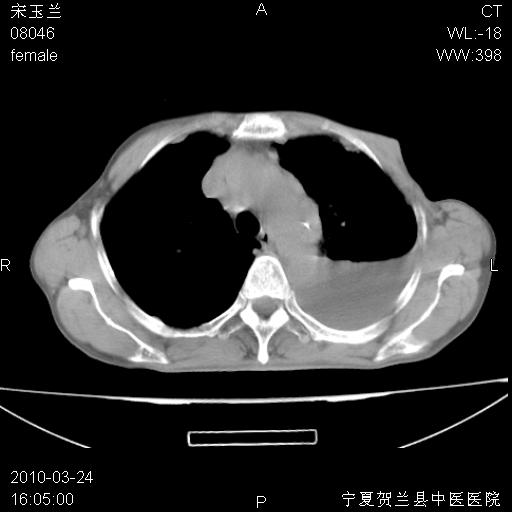

以下是引用zxl51642在2010-3-24 18:49:00的发言:[br]结合乳腺癌术后病史,考虑双肺及纵隔淋巴结多发转移、左侧胸膜转移并左侧大量胸水、左下肺膨胀不全。